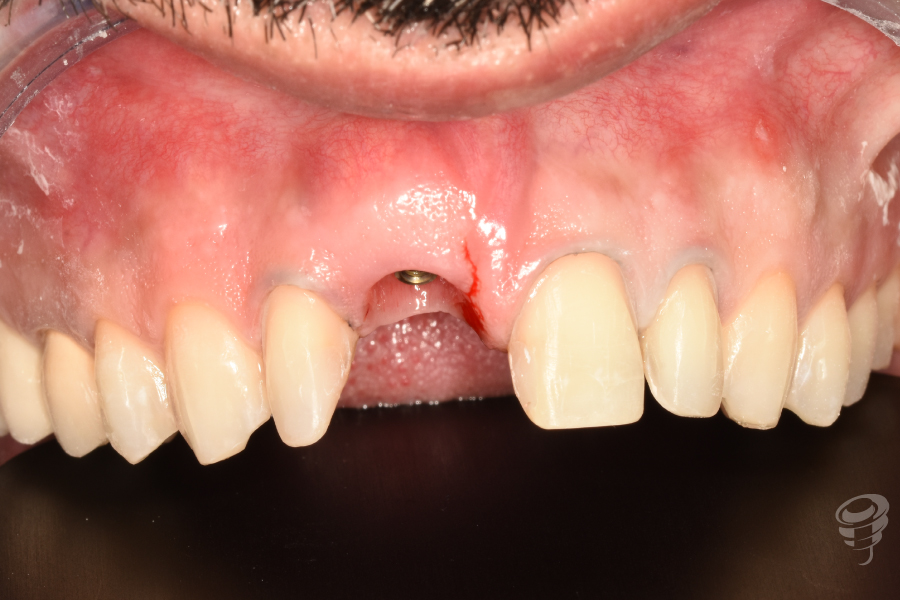

Figura 3